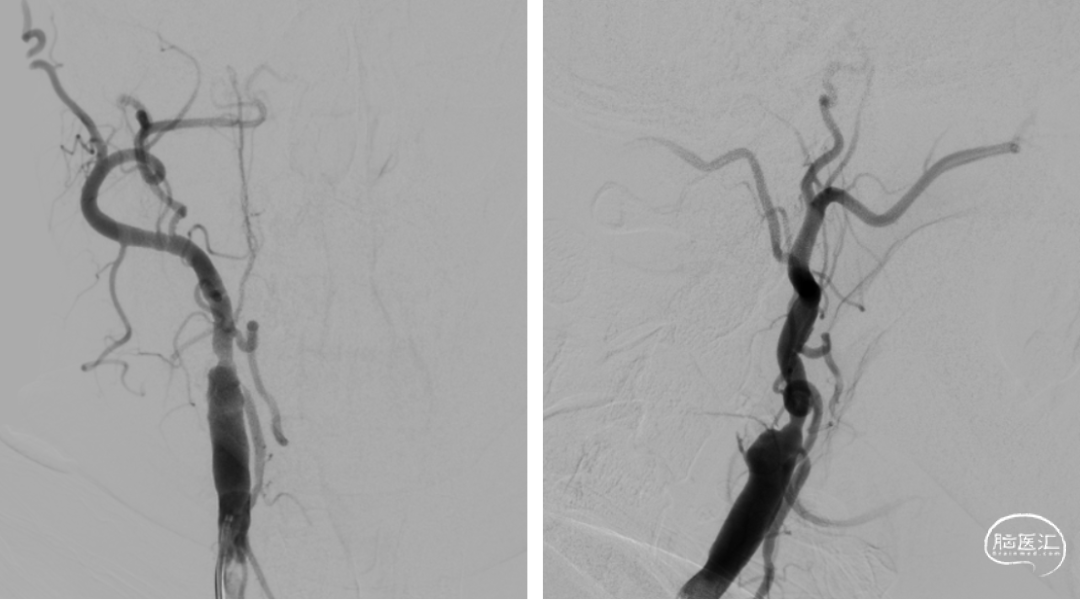

DSA提示右侧颈内动脉闭塞